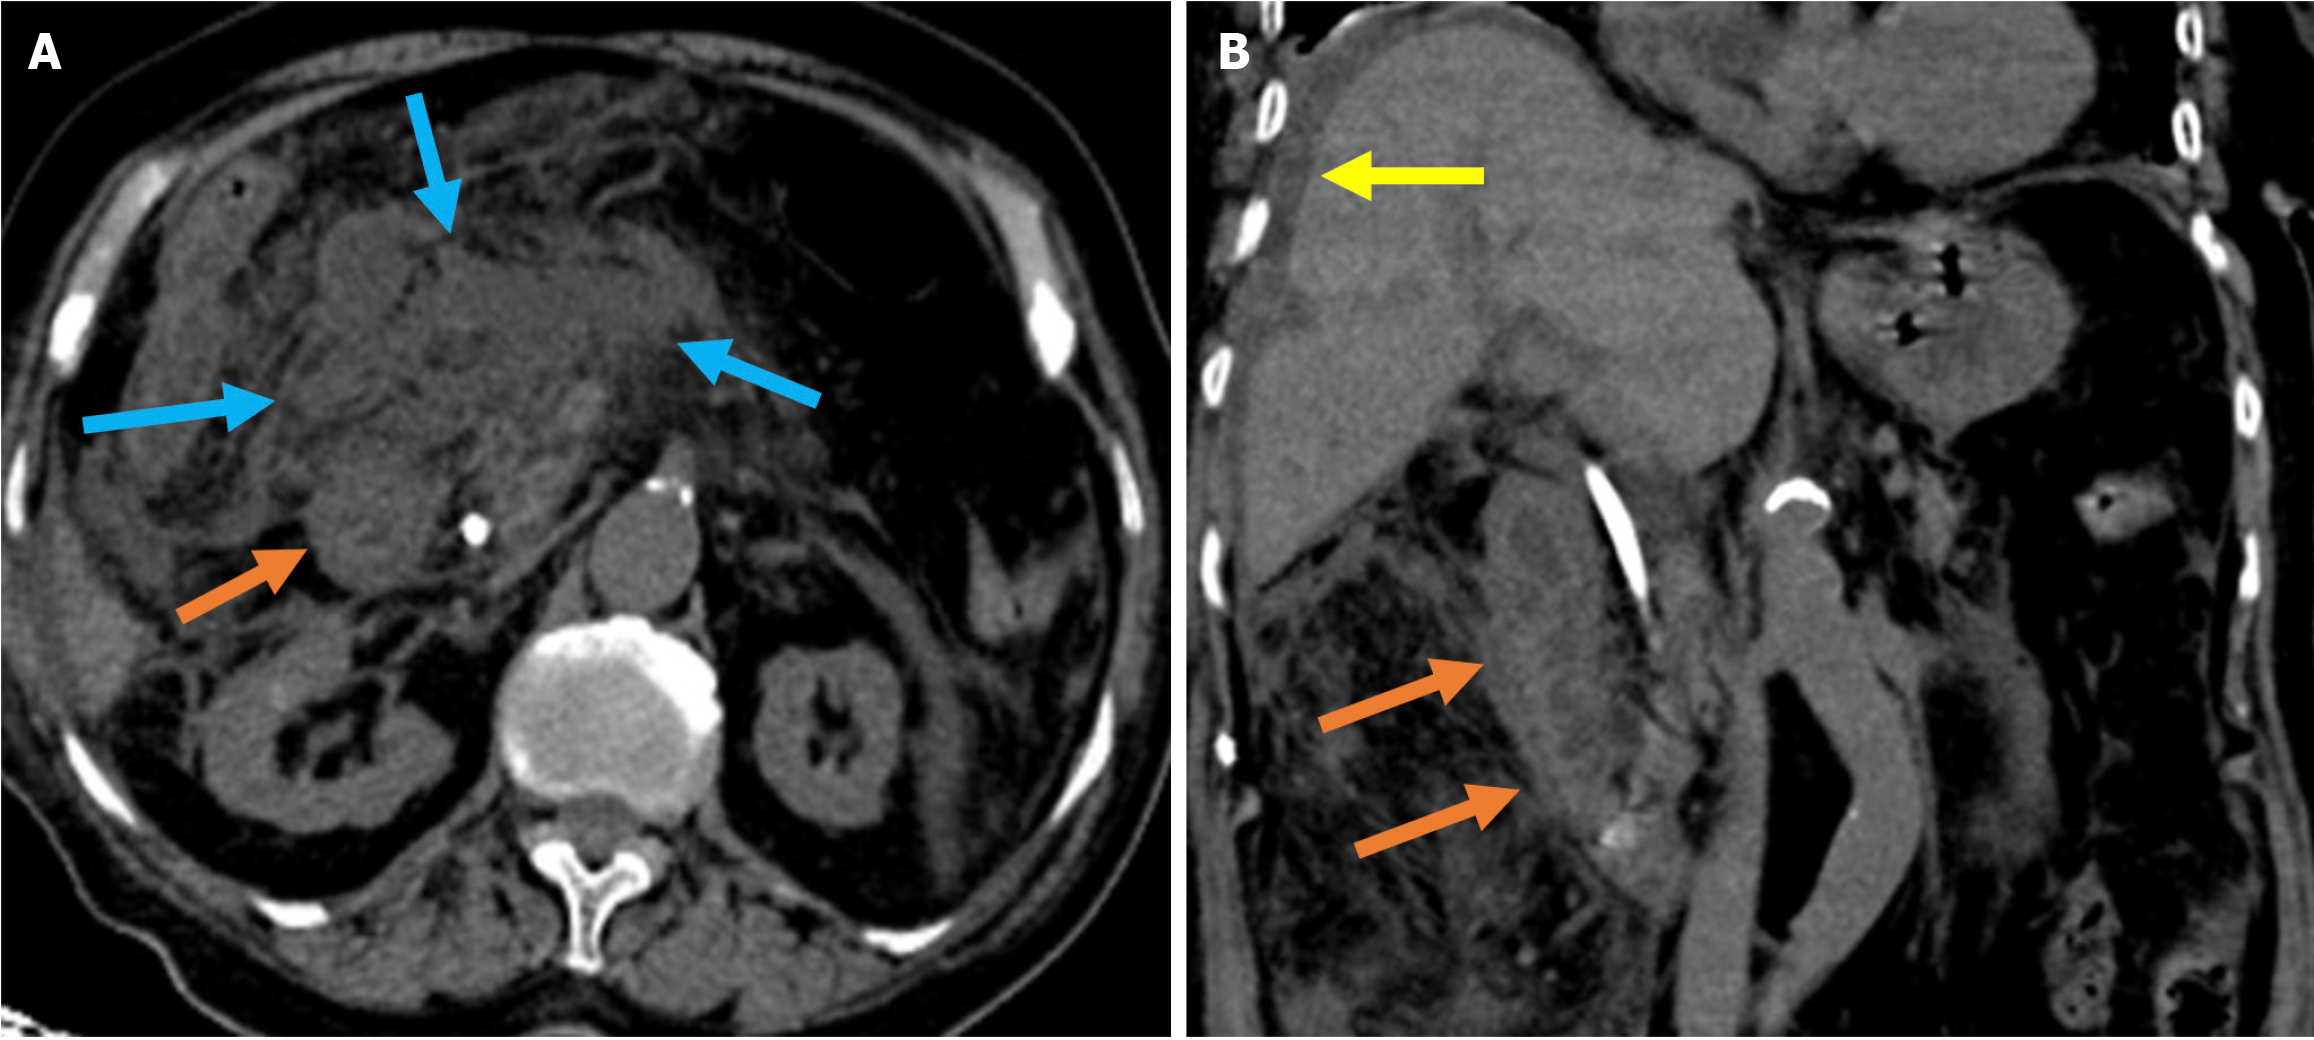

Acute duodenal wall hemorrhage appears as an area of high-attenuation wall thickening on imaging. The attenuation decreases as the hemorrhage evolves and often forms a pseudocapsule. Hyperattenuating blood can be seen within the CBD and the duodenal lumen in cases of intraluminal bleeding. Arterial phase acquisition with vascular window settings and maximum intensity projection reconstruction demonstrate active contrast extravasation in the duodenum (Figures 9 and 10)[37,61,62].

Figure 9

Figure 9 Acute duodenal wall and mesenteric hemorrhages. A and B: Axial (A) and coronal (B) noncontrast computed tomography images revealed findings consistent with hemorrhage in an 81-year-old female patient who presented with abdominal pain and a drop in hemoglobin levels following endoscopic retrograde cholangiopancreatography. A high-density mesenteric collection and mesenteric fat stranding were observed and consistent with mesenteric hematoma (blue arrows). Hyperattenuating duodenal wall thickening, indicative of an intramural hematoma (orange arrows), was also present. Free fluid was noted in the perihepatic space (yellow arrow).

Figure 10

Figure 10  Hemobilia. A and B: Axial (A) and coronal (B) noncontrast computed tomography images depicted findings of hemobilia in an 84-year-old female patient with coagulopathy who presented with abdominal pain and a drop in hemoglobin following endoscopic retrograde cholangiopancreatography. Dilatation of the common bile duct with hyperattenuating intraluminal material consistent with hemorrhage was observed (yellow arrows). Hyperdense gallstones were also visible within the gallbladder (blue arrow).